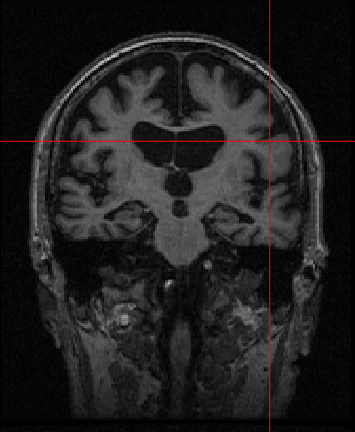

German physicist Alois Alzheimer laid the foundations of most of the modern understanding of the underlying causes of this disorder when he noticed the common biomarkers through histological techniques on the brains of his diseased patients [5]. Recent technologies exist, such as MRI, which helps in visualising atrophy or change in tissue volume of such biomarkers over a period of time, or fMRI, which can identify high-resolution activation of different brain regions during various cognitive tasks [6]. Fig. 1 shows the example of an AD patient’s raw unprocessed brain slice in different planes obtained from MR imaging in a magnetization-prepared rapid gradient-echo (MP-RAGE) sequence.

Refer to caption

(a)

(b)

(c)

Figure 1: MP-RAGE T1 Weighted MR slices: (a) Axial plane (b) Sagittal plane (c) Coronal plane